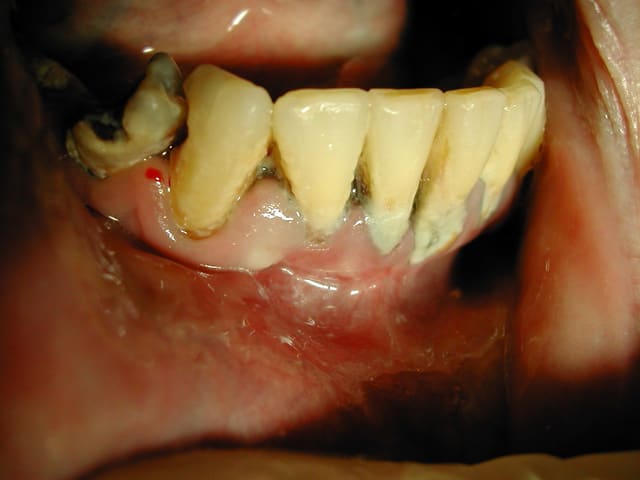

Céramik

02/10/2010 à 18h35

la semaine passée...

-Docteur, les 2 dents du centre bougent...

-Ben, on les enlèvent...

-Je ne peux pas rester sans dent, c'est pas joli...

--

Img 4156 uzbh0m - Eugenol